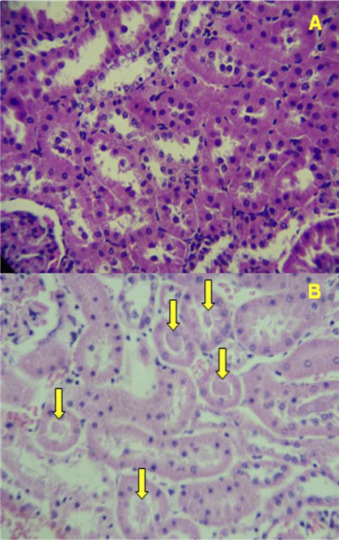

In the histopathological analysis of the organs, only the kidneys of the male and female rats treated with BCCSS presented alterations. In the kidneys of these animals, the cortical region contained amorphous eosinophilic material (cylinders) in the lumen of the proximal and distal convoluted tubules (Fig. 3 ). Discrete lymphoplasmacytic interstitial nephritis was also observed in the groups treated with CSS and BCCSS.

Fig. 3.

Cortical region of the kidneys of male Wistar rats submitted to 30 days of exposure A—kidney of the control group; B—kidney of the BCCSS group (male rat); C—kidney of the BCCSS group (female rat). *yellow arrow—amorphous eosinophilic material.

The presence of cylinders can be related to various factors, such as problems of protein reabsorption, nephritis and renal tubular lesion. This can indicate toxicity, since the formation of intratubular cylinders can obstruct the tubules and impair their function [30] . However, other examinations need to be conducted to establish the origin of these cylinders.